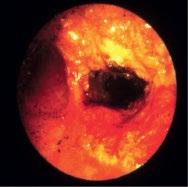

1.10 Early lung cancer. The slight discoloration on white light becomes very prominent by autofluorescence (a). By magnifying endoscopy, the pathological vascularization becomes visible (b), which is even more prominent under NBI (c). In the EBUS image, the superficial lesion ventrally is thickened (3 mm) compared to the normal wall on the left (1.4 mm), but well within the confines of the bronchiall wall and can be treated by bronchoscopic intervention (d).

1.11 Extensive squamous cell cancer at the bifurcation extending into the trachea (a). Immediately after Nd:YAG laser resection (b). Isodose lines around the Ir 192 radioactive probe (c). Bifurcation two years after HDR therapy (d). Survival of patients with complete remission compared to partial remission after HDR (e). Recurrent high-grade radiogenic stenoses after complete remission (f). Recanalization after balloon dilation by insertion of three Nitinol stents (g).